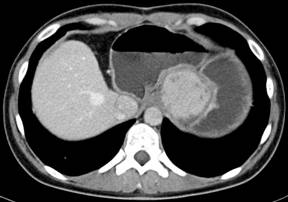

Based on this, 23 months after initial operation of the patient two recurrent metastatic fibrolamellar hepatocellular tumors were for the first time found and excised at the Department of Hepatobiliary Surgery and Liver Transplantation, Marie Curie Hospital in Szczecin, Poland where the surgical treatment was continued. The recurrences were located in the lymph nodes adjacent to the pancreatic head (6x5 cm) and in the left retroperitoneal space (7x6 cm). Eighteen months later, a tumor (3x3.5 cm) located within the hepatoduodenal ligament and compressing the portal vein was detected (Figure 1). The treatment consisted of a local tumor excision combined with a Roux-en-Y hepaticojejunostomy, as the transection of the common bile duct was necessary for complete tumor removal. The pathologic examination confirmed the diagnosis of metastatic fibrolamellar hepatocellular carcinoma. Sixteen months after the third operation, another metastatic fibrolamellar hepatocellular tumor (5x4 cm) was found (Figure 2) and excised from the space located between the lesser curvature of the stomach and the left diaphragm. This was followed by a CT scan detecting an isolated left intrathoracic nodule 13 months after the fourth operation. The tumor measured about 4 cm in diameter and was located directly above the diaphragm and very close to the caval vein (Figure 3). Resection of this nodule was done at 72 months of follow-up using a left posterior thoracotomy and the pathologic diagnosis of metastatic fibrolamellar hepatocellular carcinoma was confirmed.

Figure 2. Abdominal CT scan showing a tumor located between the lesser curvature of the stomach and the left diaphragm which was diagnosed 57 months following initial surgery. |